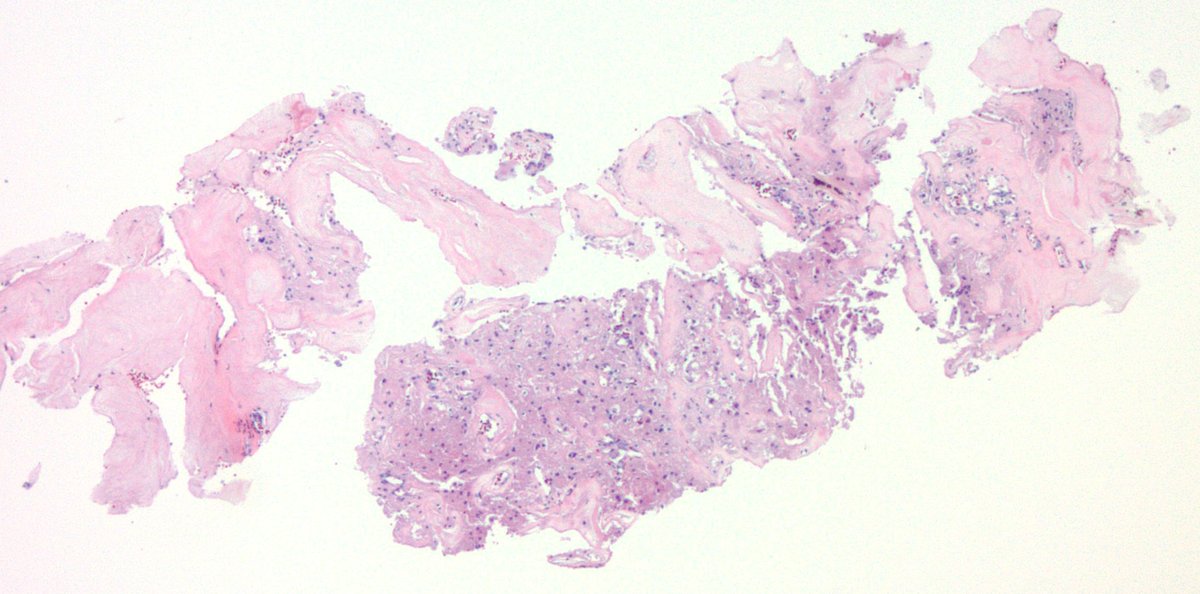

Oh Boy! This is a stunner. Pancreatic tumor. Youngish person. Diffusely keratin positive. Was called a poorly differentiated carcinoma. Sounds reasonable? #GIpath

Vik_deshpandeMD's tweet image. Oh Boy! This is a stunner.  Pancreatic tumor. Youngish person. Diffusely keratin positive. Was called a poorly differentiated carcinoma. Sounds reasonable? #GIpath